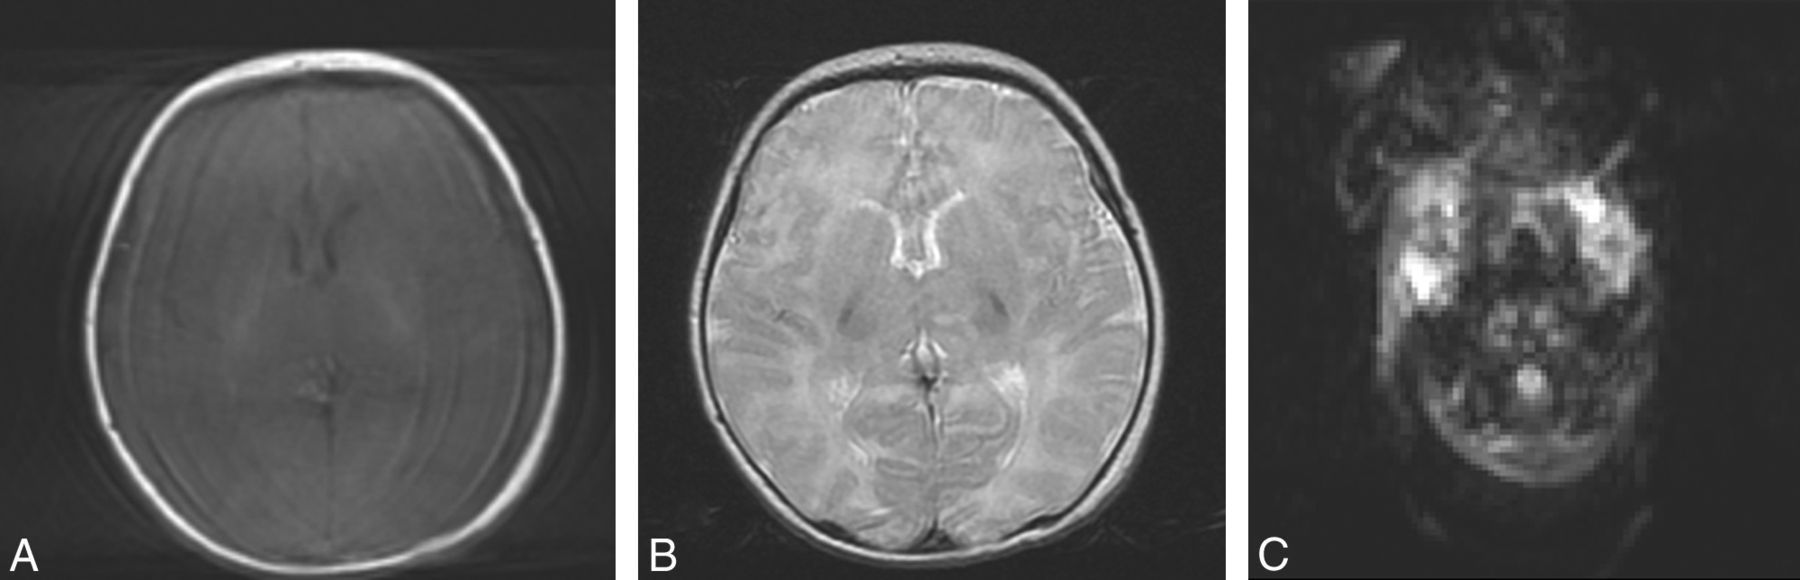

MR imaging is an ideal diagnostic technique for the evaluation of infants and fetuses1⇓⇓⇓⇓⇓–7 because of the absence of ionizing radiation, the superior contrast of soft tissues compared with sonography, and the availability of different contrast options (T1-weighted, T2-weighted, and diffusion-weighted imaging, Fig 1) to improve characterization of both anatomy and pathology. However MR imaging remains a relatively slow technique, with scanning times for most applications in the order of seconds to minutes, leaving them susceptible to motion artifacts. The normally mobile fetus and the unsettled neonate present a major difficulty because the presence of motion during a long acquisition will decrease image quality in the form of motion artifacts (Fig 2), hamper accurate image interpretation, and often necessitate a repeat MR imaging to establish a diagnosis. This may have major emotional implications for parents and can stress the tight budgets of health care providers.

T1-weighted (A), T2-weighted (B), and diffusion-weighted (C) axial MR brain images of a 5-day-old full-term neonate without motion artifacts acquired at 1.5T.

T1-weighted (A), T2-weighted (B), and diffusion-weighted (C) axial MR brain images of a 14-day-old full-term neonate acquired at 1.5T. Motion artifacts in the form of high-signal-intensity ghosts can be seen.